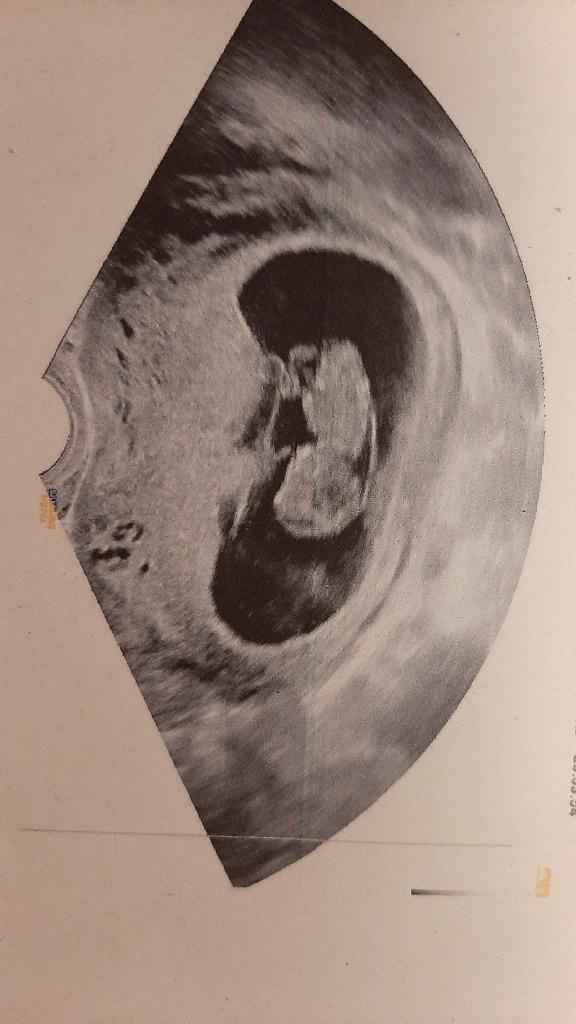

Ciao mi aiutate a capire? Ieri fatta ecogr.a 13+3. Secondo voi?Metodo Ramzi pareri 2

Lulù per favore poi giuro che non ti stresso più. Qui invece? Maschio o femmina?

Altra eco oggi .. si vede meglio..

Ciao a tutte...anche io mercoledi afaccio 7+2 ho fatto la prima ecografia (interna)..secondo voi cosa potrebbe essere? Maschietto o femminuccia?